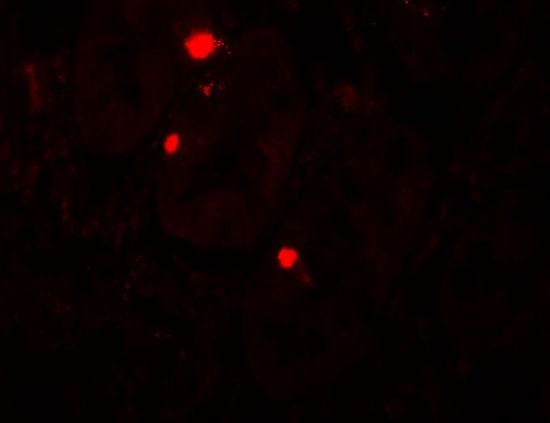

IHC-P analysis of human small intestine tissue using GTX31498 ATG14 antibody.

Working concentration : 20 μg/ml